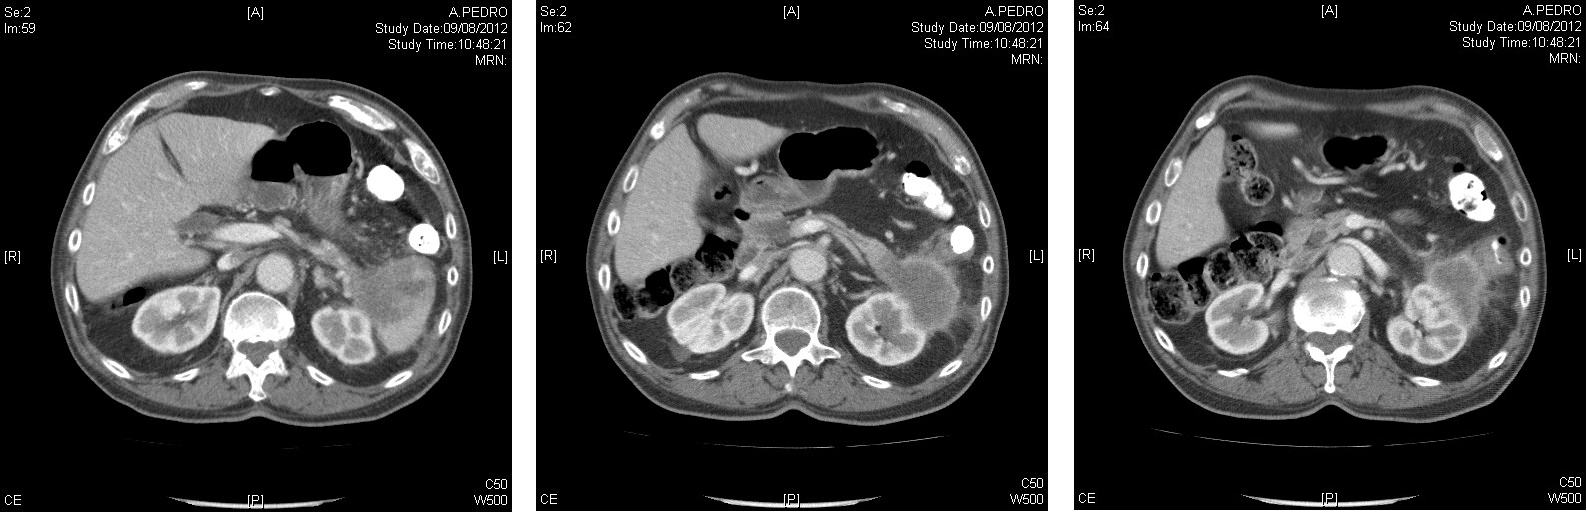

En TAC abdominopélvico se observa una masa de 5×4 cm de apariencia quística en cola pancreática que infiltra el polo inferior del bazo, el mesocolon descendente con dudosa afectación de la pared del colon, invade el espacio perirrenal y contacta con la cara anterior del riñón izquierdo sin establecerse un límite claro de separación. No se objetivan adenopatías mesentéricas y retroperitoneales.

Fig 1-3: TAC abdominopélvico.